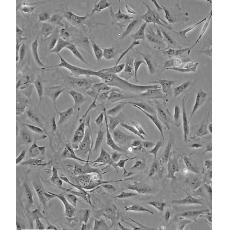

3T3-L1

中文名稱 小鼠前脂肪胚胎成纖維細(xì)胞

組織來源 胚胎;成纖維;自發(fā)永生;雄性;Swiss albino

形態(tài)特征 成纖維細(xì)胞樣

生長特性 貼壁生長

特征特性 3T3-L1是從3T3細(xì)胞(Swissalbino)中經(jīng)克隆分離得到的連續(xù)傳代的亞系。該細(xì)胞從快速分裂到匯合和接觸性抑制狀態(tài)經(jīng)歷了前脂肪細(xì)胞到脂肪樣細(xì)胞的轉(zhuǎn)變。該細(xì)胞鼠痘病毒陰性;可產(chǎn)生甘油三酯,高濃度血清可增強細(xì)胞內(nèi)脂肪堆積。

培養(yǎng)條件 DMEM(高糖)+10%FBS

傳代方法 1:2傳代